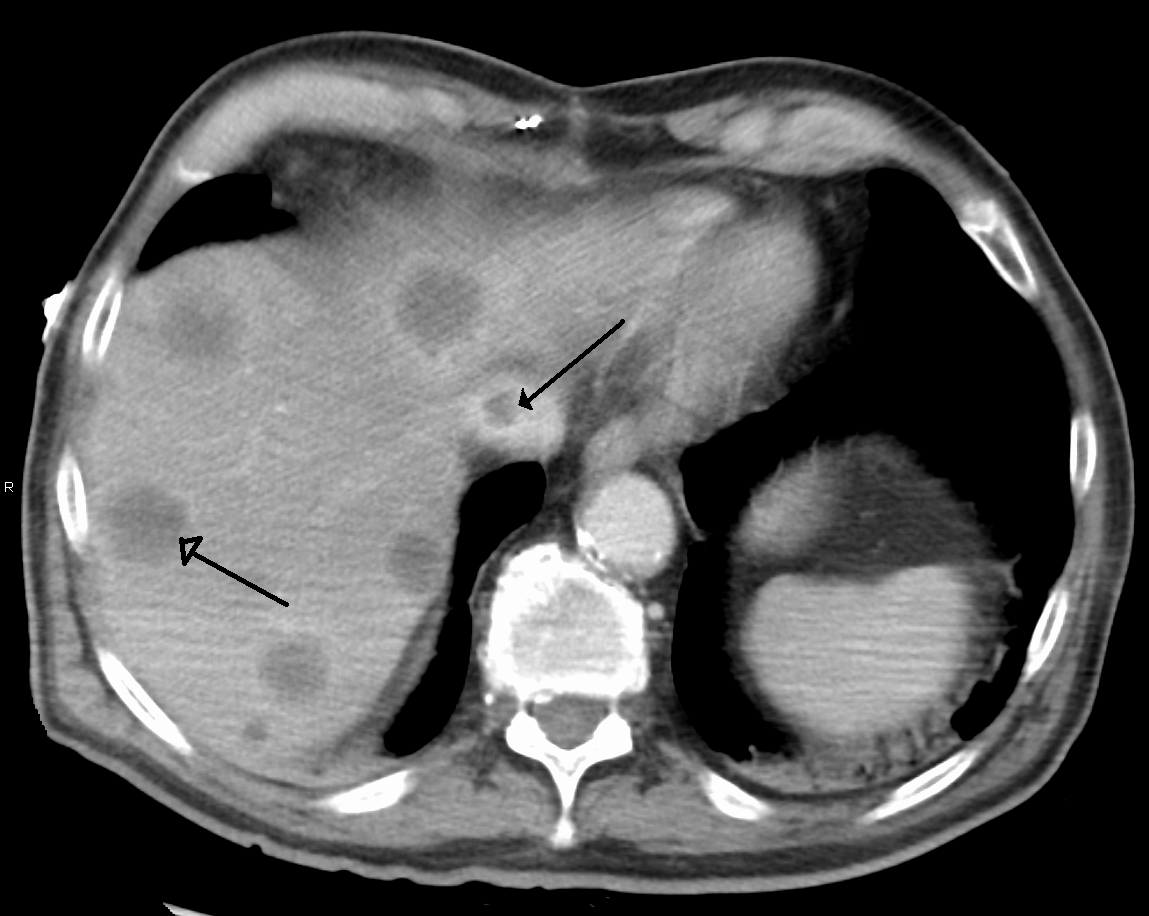

간 기능 검사, 영상 검사, 간 생검 등 다양한 검사를 통해 간 질환을 진단할 수 있다. 간 기능 검사는 혈액 내 효소, 대사 물질, 생성물 등을 검사하는 방법이다.[46] 영상 검사는 일시적 탄성 측정법, 초음파, 자기 공명 영상(MRI) 등을 통해 간 조직과 담관을 확인하는 방법이다.[47] 간 생검은 간 조직을 직접 검사하여 질환을 구별하는 방법이다.[47]

5. 0. 2. 영상 검사

일시적 탄성 측정법, 초음파 및 자기 공명 영상(MRI)과 같은 영상 검사를 사용하여 간 조직과 담관을 볼 수 있다. 다양한 상태를 구별하기 위해 간 조직을 검사하는 간 생검을 수행할 수 있다. 탄성 측정법과 같은 검사를 통해 일부 상황에서 생검의 필요성을 줄일 수 있다.[47]5. 0. 3. 간 생검

일시적 탄성 측정법, 초음파, MRI와 같은 영상 검사를 통해 간 조직과 담관을 확인할 수 있다. 간 생검은 간 조직을 직접 검사하여 다양한 간 질환을 구별하는 데 사용될 수 있다. 탄성 측정법과 같은 검사는 일부 경우 간 생검의 필요성을 줄일 수 있다.[47]5. 0. 4. 기타 검사